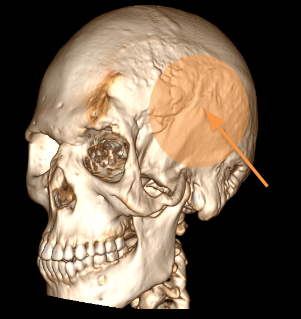

Computed tomography

Contrast-enhanced axial CT

- Soft tissue density mass, involving the superficial layers of the left hemiface, apparently originating from the cutaneous and subcutaneous tissues.

- The mass is composed of nodular material with heterogeneous attenuation. The nodules have hyperdense contours and predominantly hypodense internal contents with heterogeneous enhancement.

- Irregularity in the cranial skull with thinning and remodeling.

- There was no intracranial extension.